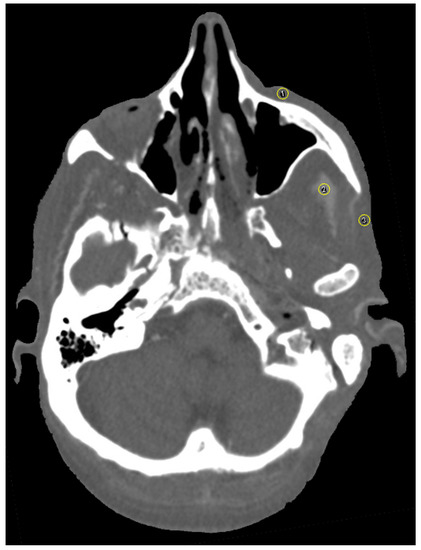

3.1. Streak Artifacts

3.1.1. Implant Material

3.1.2. Metallic Artifact Reduction Algorithm

3.2. Blooming Artifacts